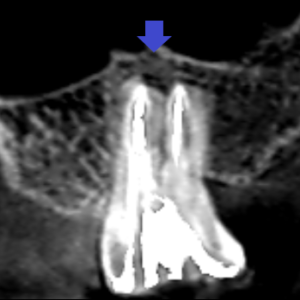

精密根管治療6カ月後の経過観察時の近心頬側根の冠状断のCT画像です。

石灰化し未治療だった根管も根の先まで根管充填されています。

矢印の先の根の先にあった膿の影が消失し、歯槽骨が再生しています。